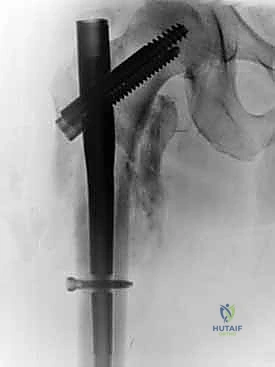

يتكون هذا النظام الجراحي من:

1. المسمار النخاعي الرئيسي (Intramedullary Nail): مسمار طويل يمتد داخل القناة النخاعية لعظمة الفخذ.

2. المسمار الرأسي/العنقي (Cephalic/Lag Screw): مسمار سميك وقوي يمر من خلال الجزء العلوي للمسمار النخاعي، ويدخل في عنق ورأس عظمة الفخذ لتثبيت الكسر الرئيسي.

3. مسامير الغلق السفلية (Distal Locking Screws): مسامير صغيرة تُثبت أسفل المسمار النخاعي لمنعه من الدوران أو الانزلاق داخل العظم.

هذا التصميم العبقري يجعله أقوى نظام تثبيت متوفر حالياً، حيث يمر محور تحمل الوزن عبر المسمار الموجود داخل العظم، مما يجعله مقاوماً للكسر والانحناء، ويسمح للمريض بالاعتماد على ساقه في وقت قياسي.

5. تثبيت عنق ورأس الفخذ (المسمار الرأسي)

من خلال ذراع توجيه متصلة بالمسمار الرئيسي، يتم إحداث ثقب في عنق ورأس عظمة الفخذ. يتم إدخال المسمار الرأسي (Cephalic Screw) السميك ليمسك برأس الفخذ بقوة ويسحبه نحو المسمار الرئيسي، مما يضغط الكسر (Compression) ويحفز التئام العظام بسرعة.